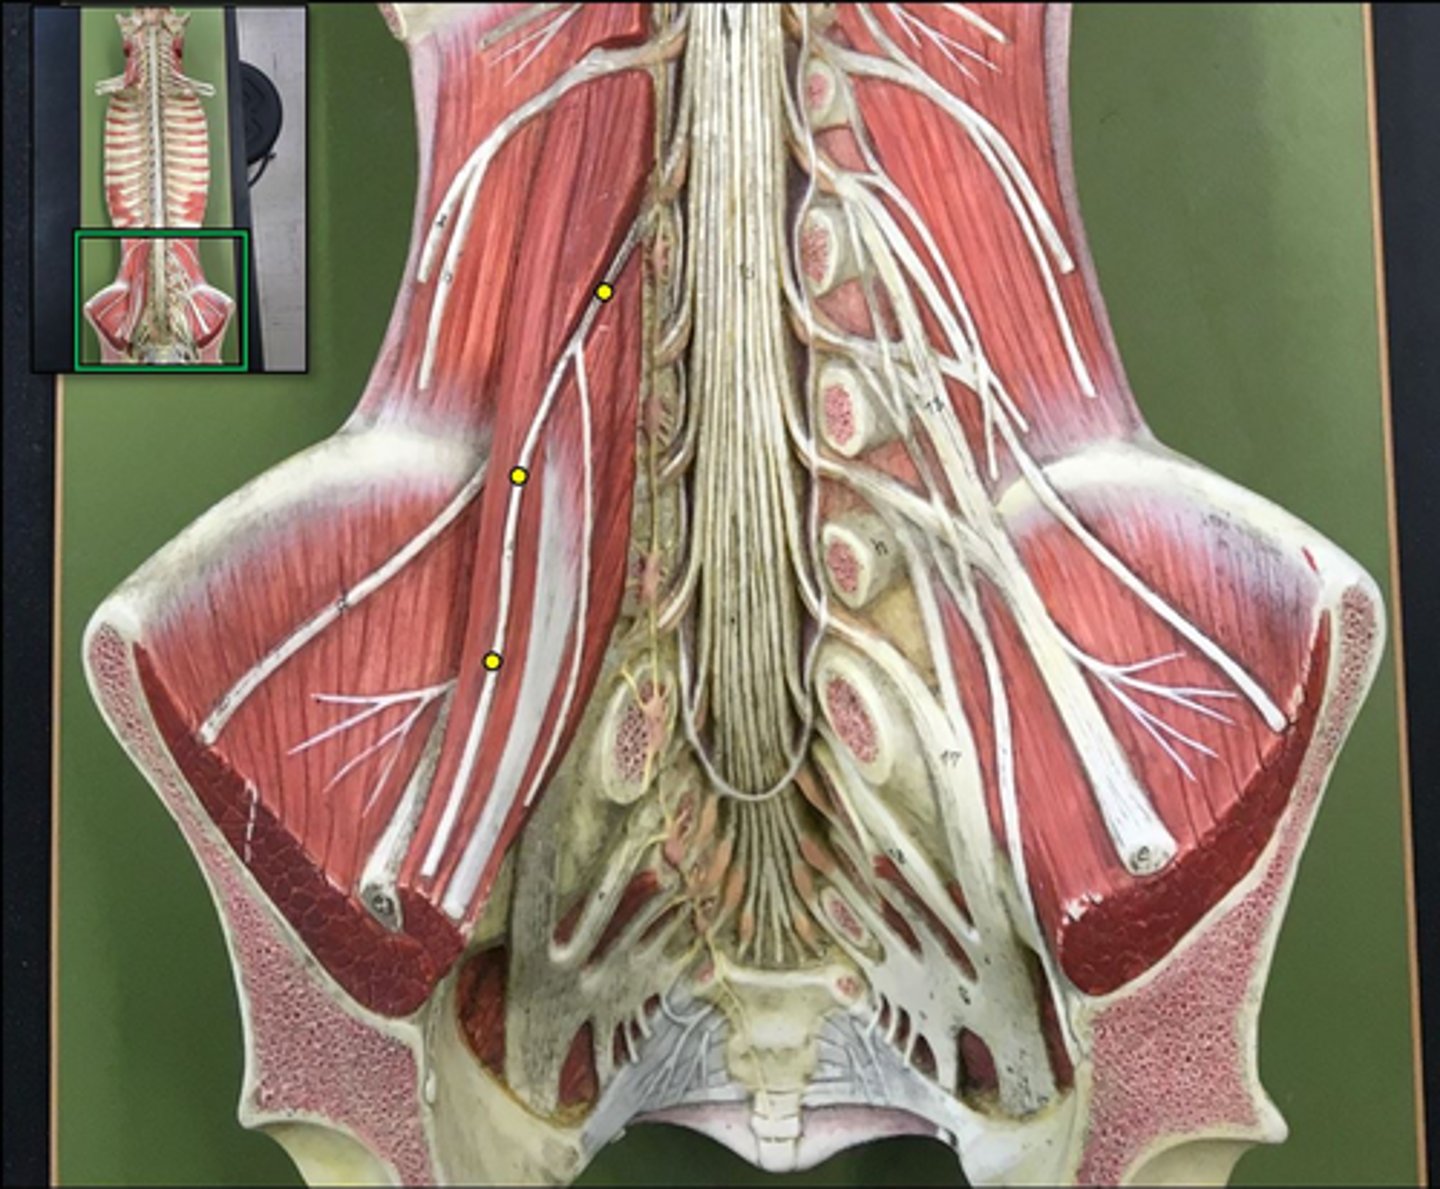

lumbar plexus

T12- L4

sacral plexus

L4- S4

genitofemoral nerve

Wishbone of the leg

lateral femoral cutaneous nerve

femoral nerve

saphenous nerve

posterior femoral cutaneous nerve

sciatic nerve

obturator nerve

common fibular nerve

tibial nerve